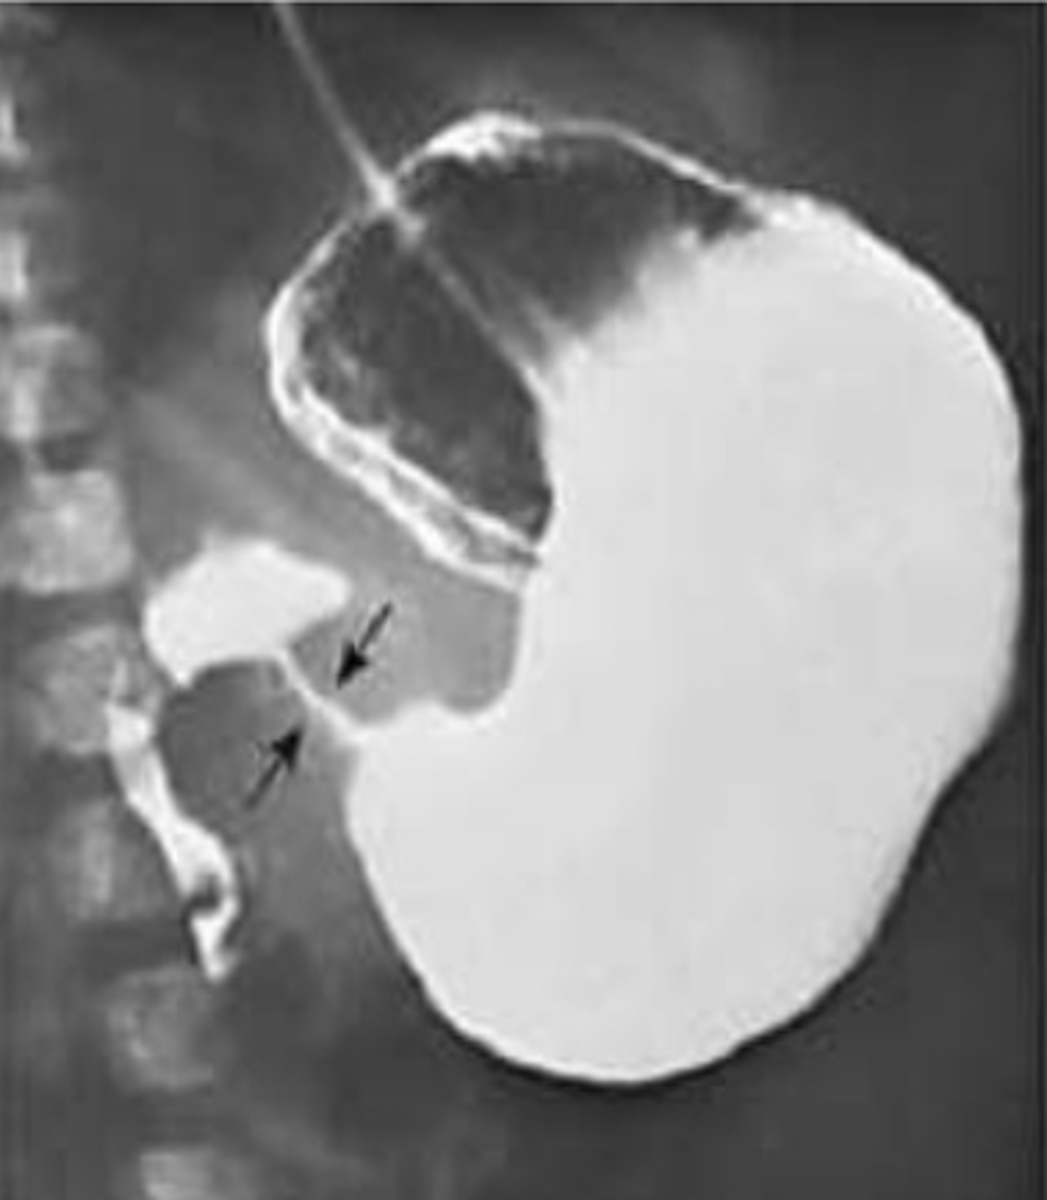

What is intussusception, & where is the most common area for this to occur? What is the most common lead point (trigger) for this?

Telescopic invagination of the bowel lumen resulting in obstruction; ileocolic junction; viral infection

What are some s/sxs of intussusception?

Bouts of severe colicky abdominal pain (interspaced by periods of lethargy), vomiting, blood in the stool ("currant jelly stool" = buzzword), possible sausage-shaped mass on PE

What is the best initial test for intussusception, & what will be seen? What is the best overall test for this condition?

Initial: ultrasound (shows "target sign")

Best: air contrast enema (both diagnostic & therapeutic)

How is intussusception treated?

Supportive care, air enema is ideal first & surgery can be done if this fails